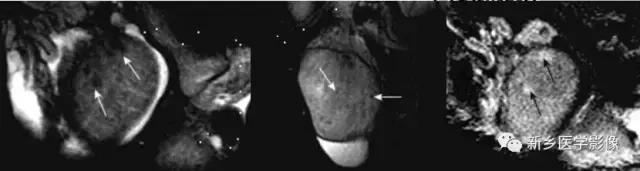

MR:精原细胞瘤各信号偏低、均匀、散在,恶性病变,信号可不均;非精原细胞瘤信号不均

MR:洋葱环样改变,高低信号较低轮带状改变,增强扫描无明显强化。